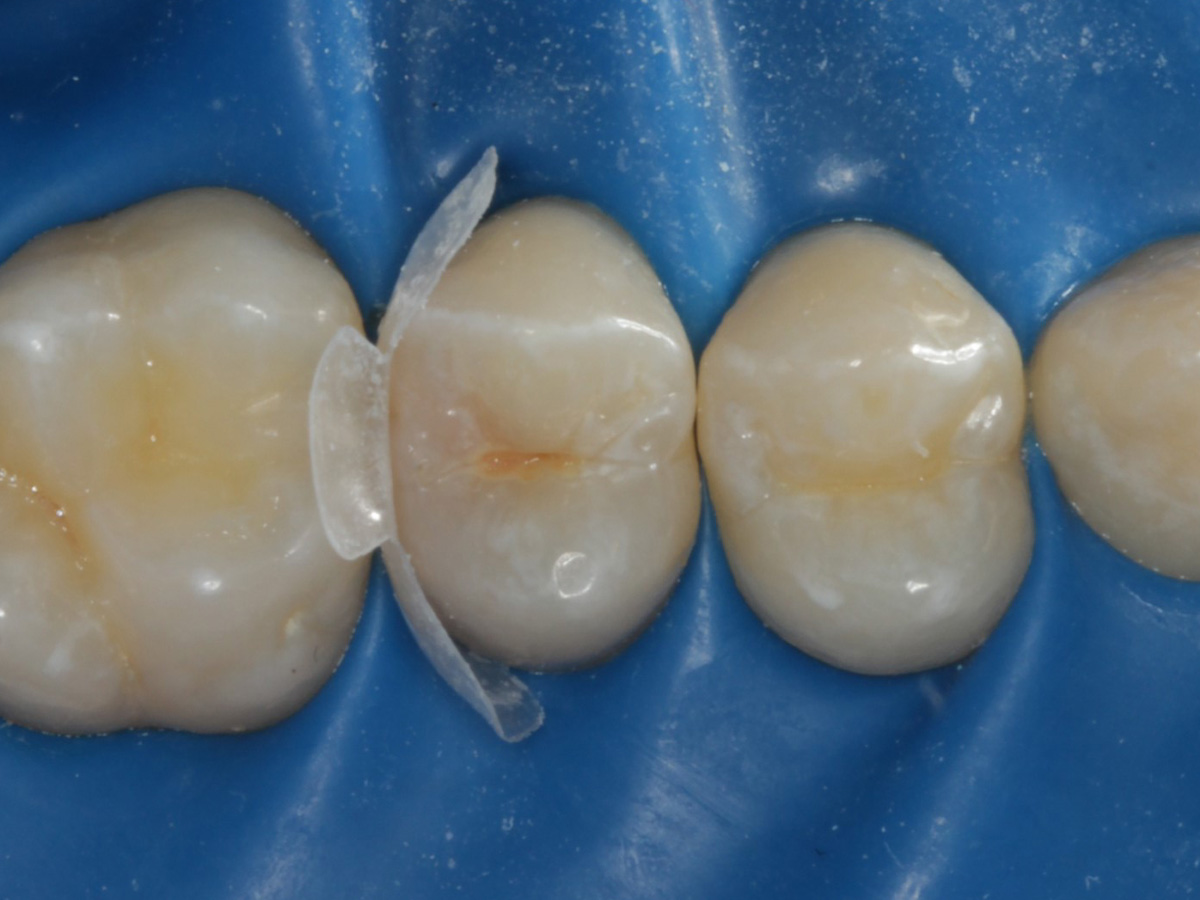

Abbildung 3

Quadrantenisolierung mit Kofferdam (x-heavy)